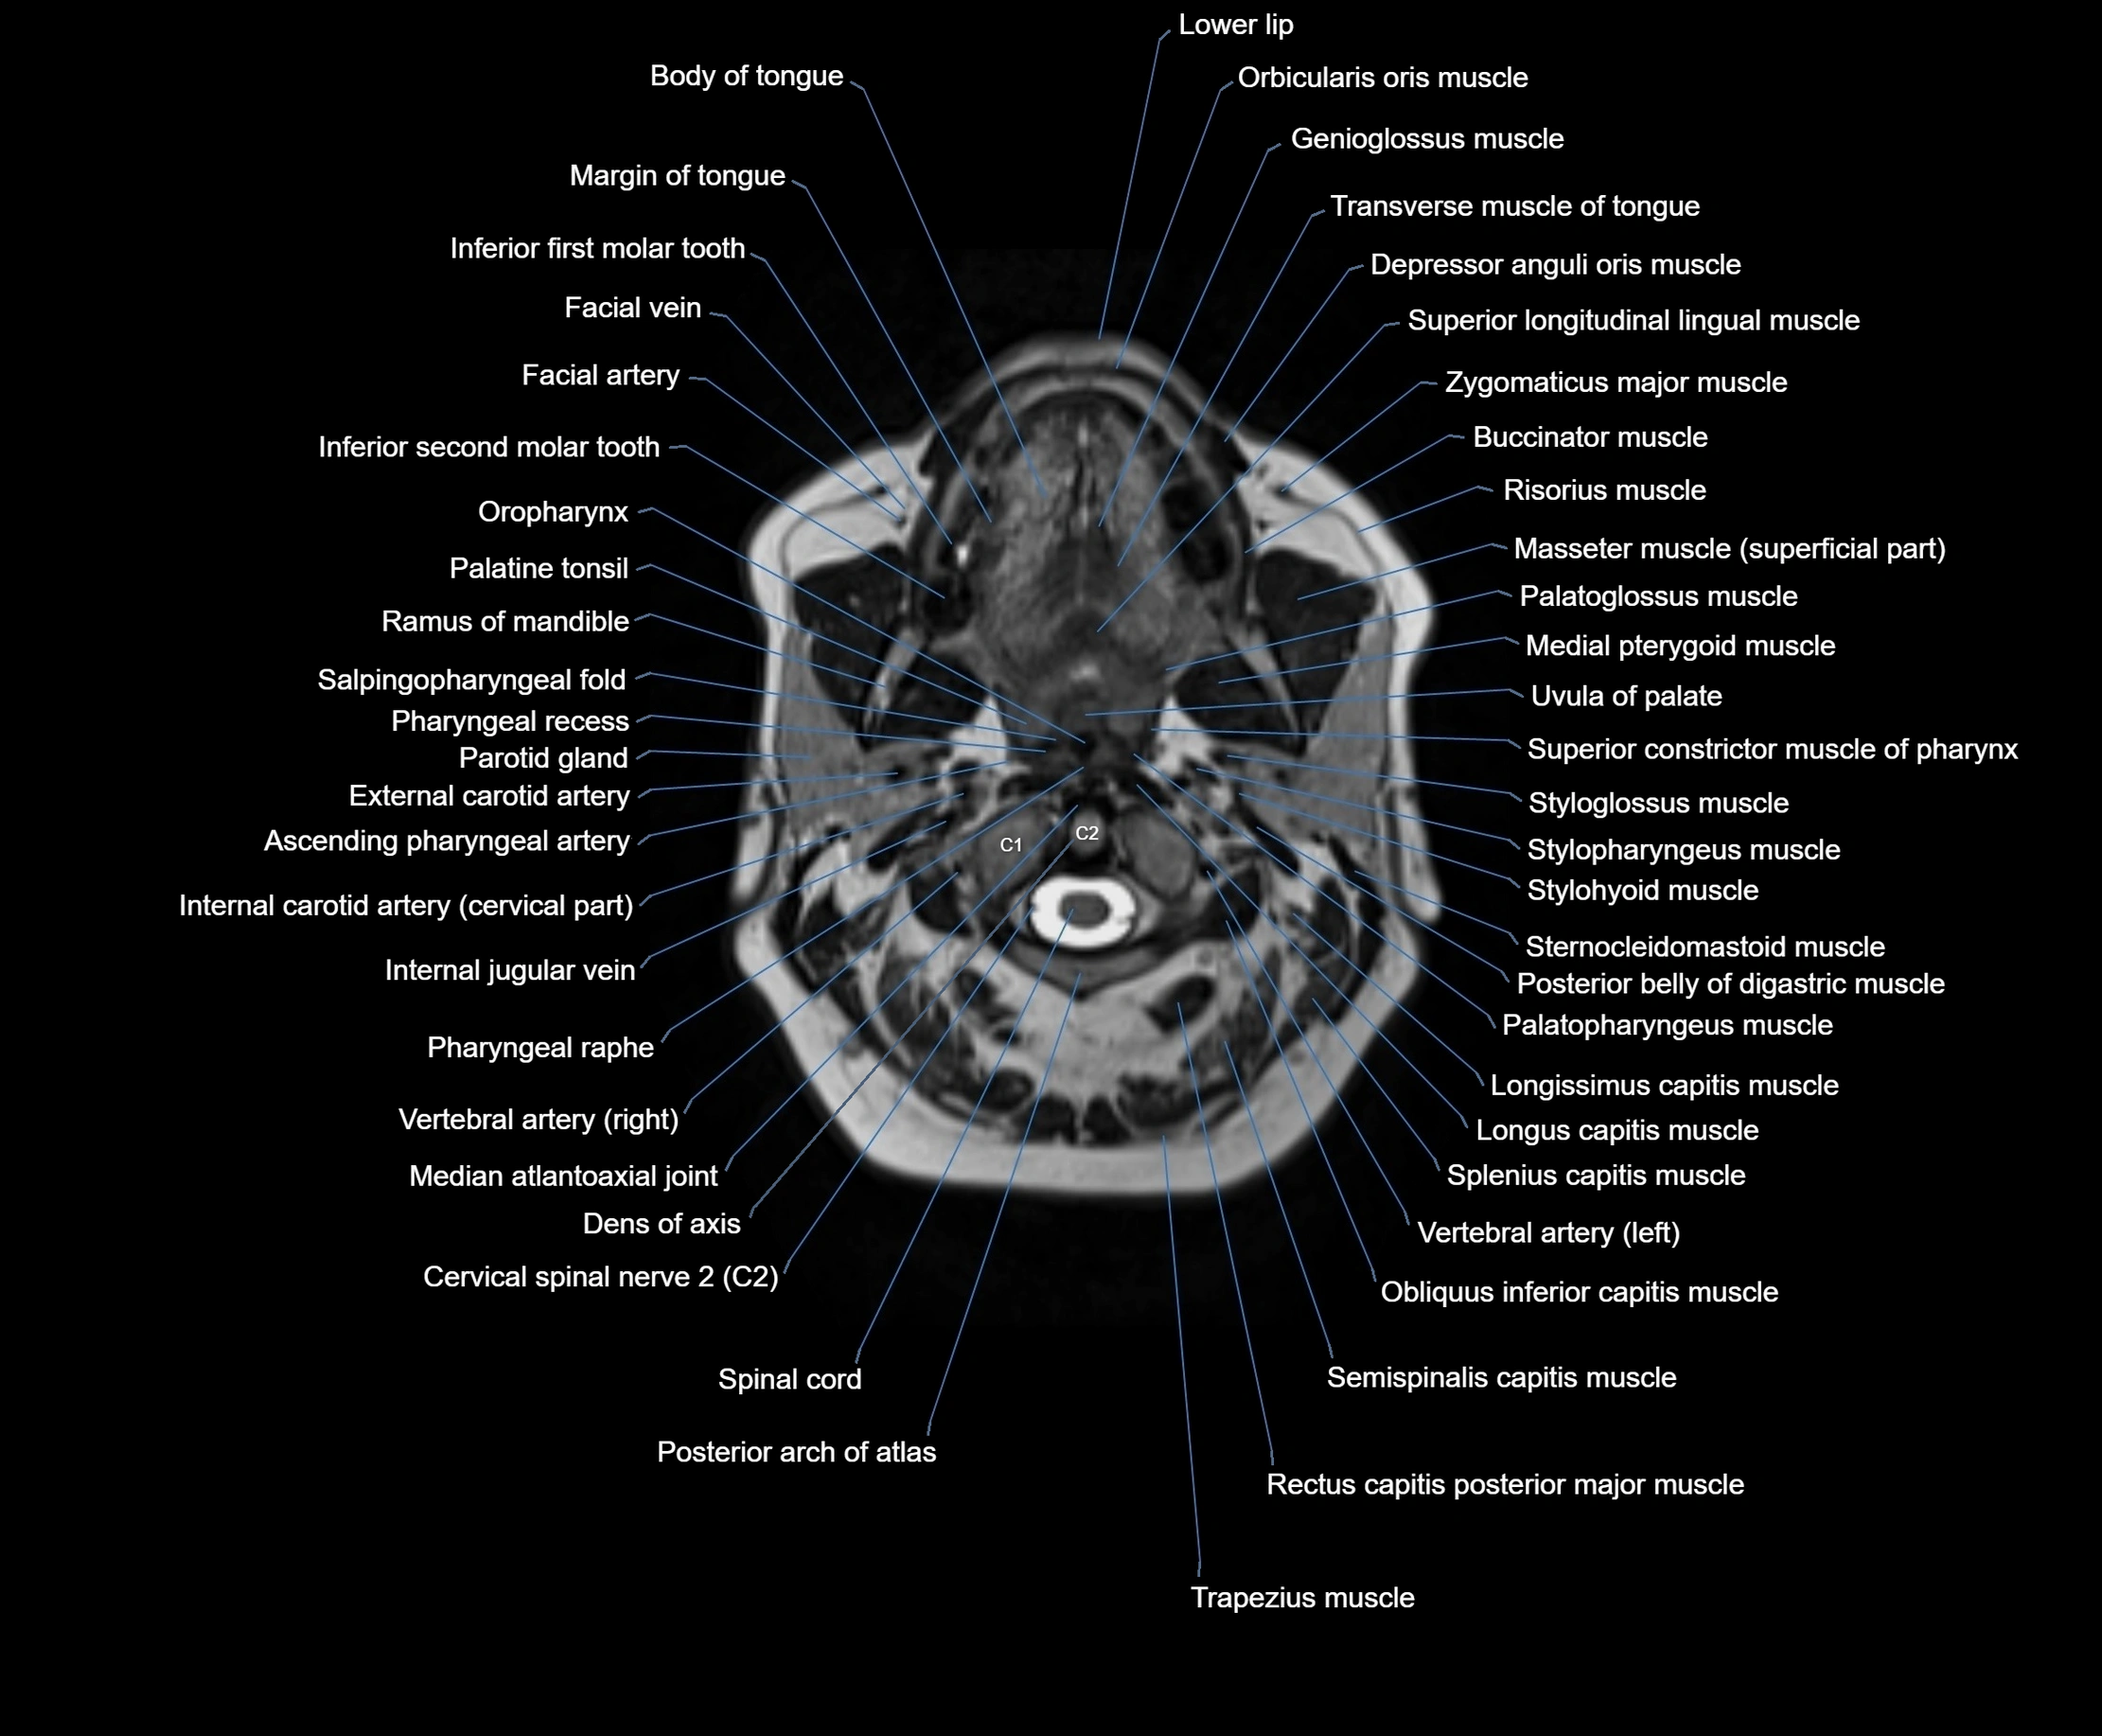

- Ascending pharyngeal artery

- Cervical spinal nerve 2 (C2)

- Dens of axis

- Internal carotid artery (cervical part)

- Median atlantoaxial joint

- Obliquus inferior capitis muscle

- Pharyngeal raphe

- Posterior arch of atlas

- Semispinalis capitis muscle

- Spinal cord

- Splenius capitis muscle